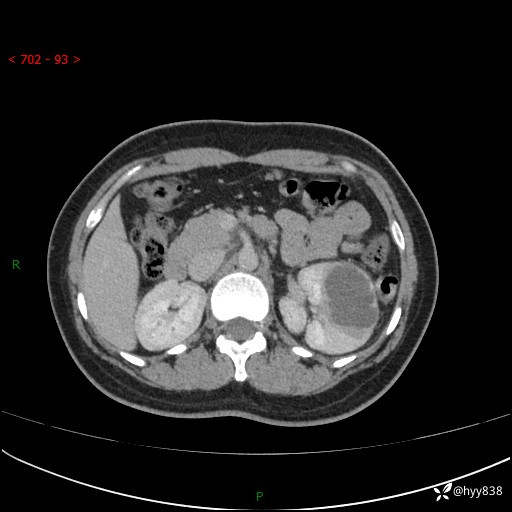

现病史:患者于1周前因左侧腰腹部间断胀痛不适,无恶心呕吐,无明显肉眼血尿,无畏寒发热,无尿频尿急,起病初,患者来我院就诊,查CT提示左肾低密度影,外周血提示:白细胞11.25*10^9/L.行抗感染治疗后未见明显好转,06-18泌尿系增强CT提示左肾类圆形低密度占位(脓肿?肿瘤?),大小:4.0*3.2cm,为求进一步治疗,门诊以“左肾占位”收住我科。 起病以来,患者精神佳,饮食、睡眠良好,大小便正常,体力体重无明显变化。

双肾CT平扫+增强